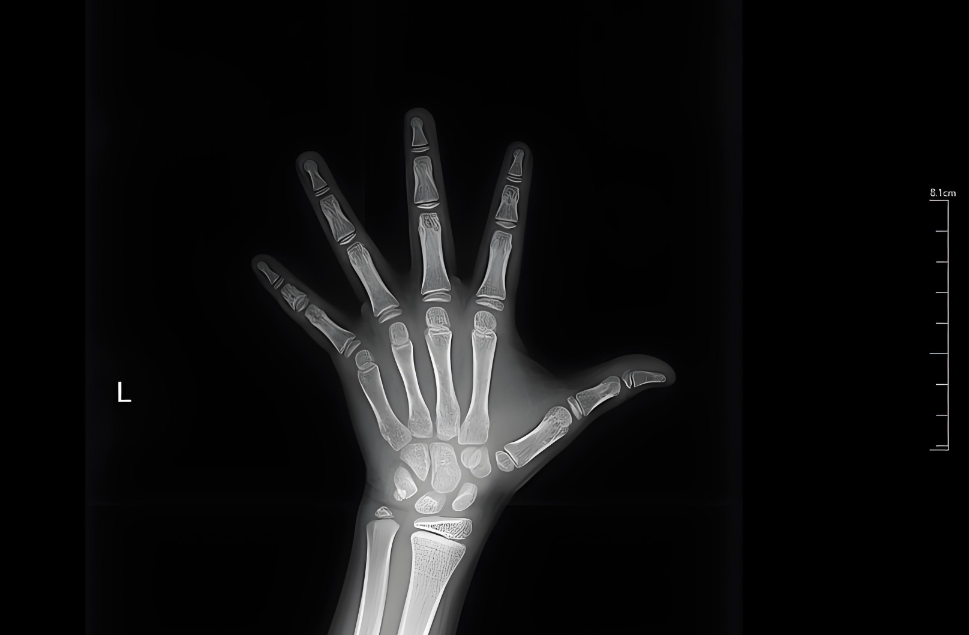

骨龄检测:成长计时器

就像树木的年轮,手腕X光片能准确显示骨骼的"年龄"。比如实际年龄 10 岁,骨龄却 12 岁,说明生长时间已减少 2 年,需紧急干预。建议:

• 6-8岁做第一次检查;

• 体重超标孩子每半年复查;

• 发现骨龄超前要及时干预。